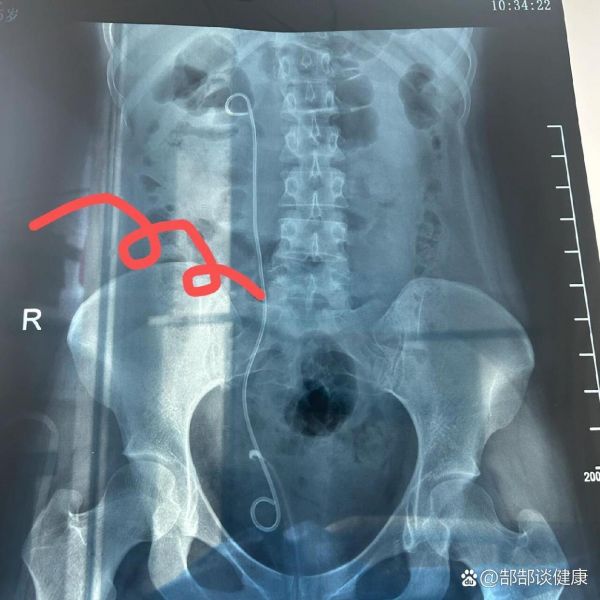

记输尿管开口囊肿之术后一个月拔管♀...全文